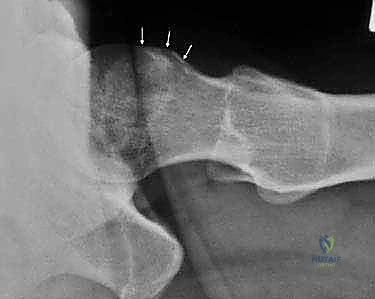

- التصوير بالأشعة السينية (X-rays): صور دقيقة بوضعيات خاصة (AP Pelvis, Dunn view, Cross-table lateral) لقياس زوايا محددة مثل زاوية ألفا (Alpha Angle) التي تؤكد وجود تشوه "كام"، وعلامة التقاطع (Crossover Sign) التي تؤكد وجود تشوه "بنسر".

صورة شعاعية قبل التدخل الجراحي توضح التشوه العظمي بوضوح.